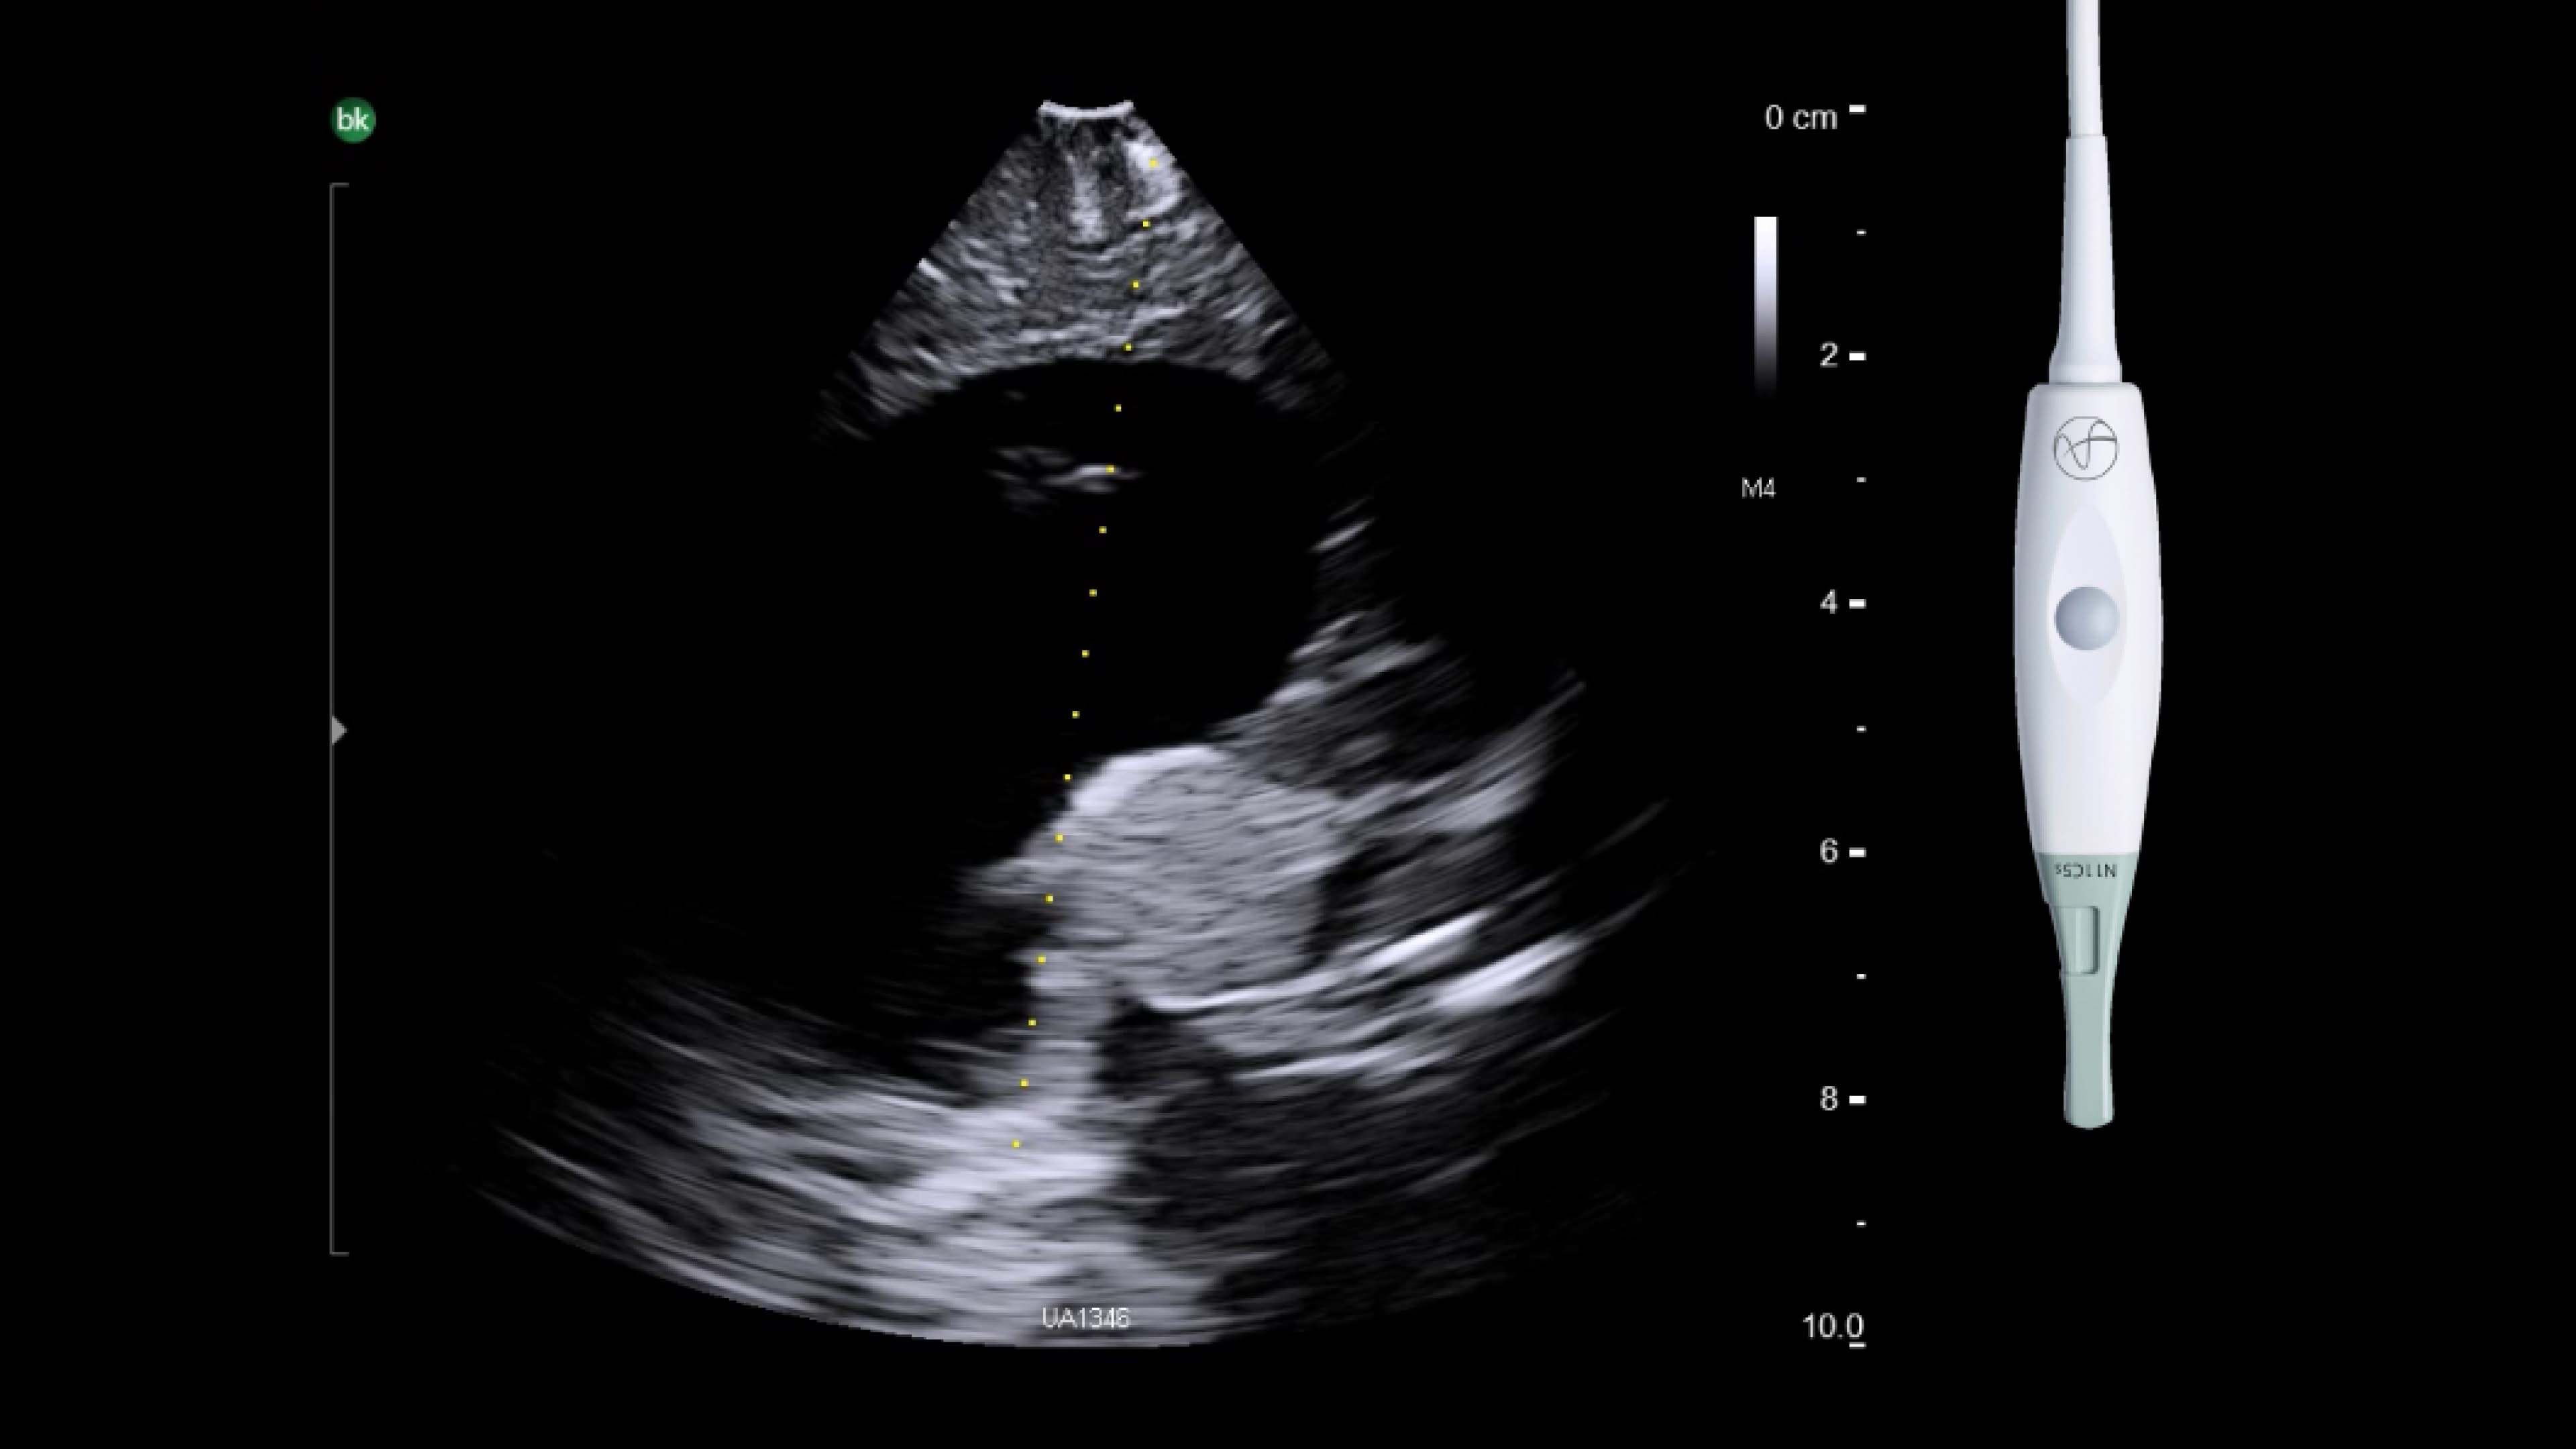

Spine

Visualize soft tissue in detail with Active Imaging. Active imaging offers real-time guidance in a variety of spinal procedures during open and minimally invasive approaches: spinal decompressions, chiari malformations, tumor resections, selective dorsal rhizotomy, anterior cervical discectomy and fusion.